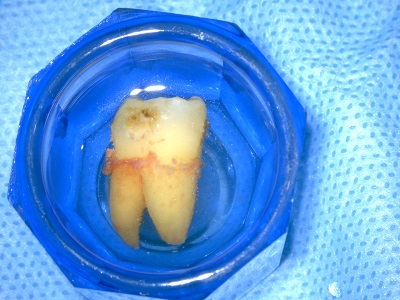

自家歯牙移植

自家歯牙移植とは、失った(失う)歯の部分の骨に、自分の他の歯(親知らずなど)を移植しかみ合わせを回復する方法です。

インプラントなどと異なり自分の組織を移植するので異物反応が起きにくく、生着するとしっかりと噛むことができます。

自家歯牙移植は移植歯(ドナーの歯)の状態と移植部位の骨の状態などがマッチした場合有効な方法です。しかしながら移植歯の歯根膜組織の扱いや移植後の固定、根管治療などを適正におこなわなければならず、しっかりとした治療計画と術中、術後管理が必要となります。

右上の親知らずを左下6番目に移植